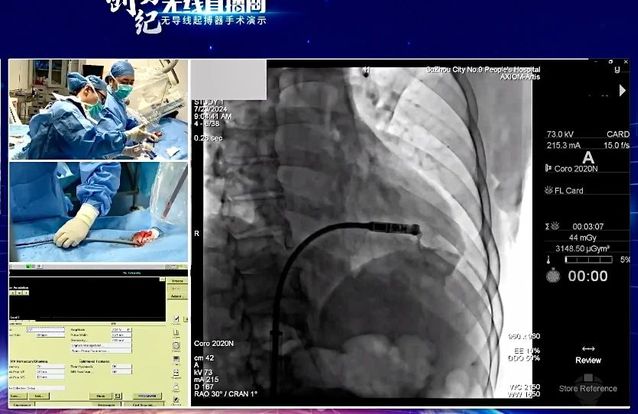

7月24日,“创势纪·无线直播间—苏皖区域无导线起搏器手术演示”在线上举行,苏州九院心血管内科主任吴雁鸣参与手术演示,助力提升区域心血管病防治水平。本次活动由江苏省医学会心血管病学分会副主任委员、苏州市心血管病学分会主任委员、苏州大学附属第一医院心内科主任蒋廷波主持,汇聚了一大批专家教授开展手术演示和线上探讨,通过学术交流积极推动苏皖地区心血管病防治水平的进一步提高。

早在2021年,苏州九院心血管内科就积极引入和开展无导线心脏起搏器植入术,是我区首家成功独立开展无导线起搏器植入手术的医院。心血管内科主任吴雁鸣是我区首位独立无导线起搏器术者,目前已成功独立植入近30例,受益人群大多为高龄老人,其中年龄最大的患者接受手术时已经103岁。

无导线起搏器,代表心脏起搏领域**技术。无导线起搏器(Micra),俗称胶囊起搏器,是目前世界上最小最轻的起搏器,直径6.7mm,长度25.9mm,重量仅1.75g,是国际前沿的先进起搏技术。虽然小,但其电池续航能力强,工作寿命长达12年,植入后还可以接受1.5T/3.0T核磁共振检查。患者无切口、无伤疤、无凸起、无束缚,几乎感觉不到它的存在,是看不见的起搏器,就像默默守护心律失常患者心脏健康的“隐性保镖”。

这一技术的成熟推广,对区域患者健康有着重要意义。植入心脏起搏器主要针对严重缓慢性心律失常的患者。传统的心脏永久起搏器由脉冲发生器和电极导线组成,医生通过腋静脉或锁骨下静脉将起搏器电极导线送至右心房或右心室,在患者胸前区胸大肌处制作与起搏器大小合适的囊袋,以容纳脉冲发生器。无导线起搏器不同于传统起搏器的地方在于:它不需要使用导线将脉冲发生器连接到起搏电极上。相反,它将脉冲发生器和起搏电极集成在一起,以微缩胶囊的形式直接植入患者的心腔内部。